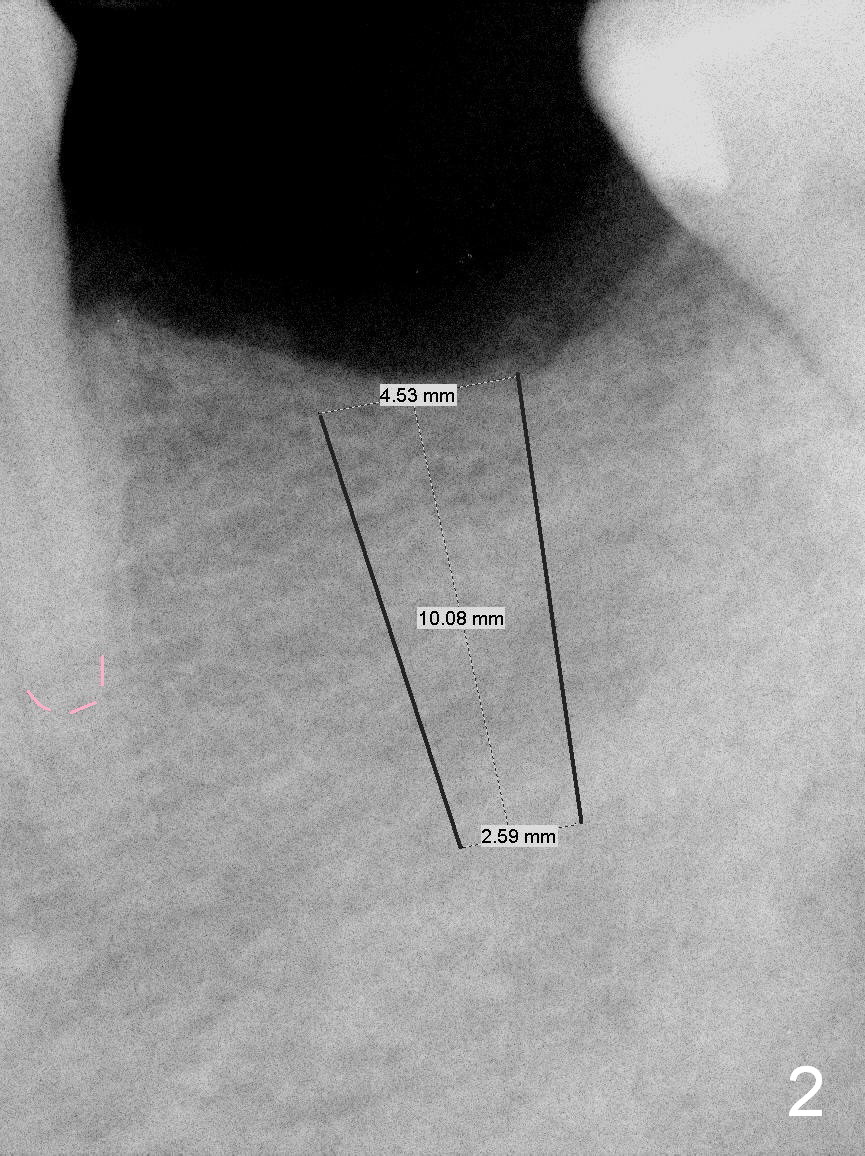

A 60-year-old man has lost the tooth #19 for approximate 20 years (Fig.1). The superior border of the Inferior Alveolar Canal is not distinct in PA. An implant that is slightly longer than the root of the neighboring tooth should be safe (Fig.2). Panoramic X-ray reveals plenty of bone height (Fig.3). Therefore, initial osteotomy depth will be 10 mm. Insert a parallel pin and take the 1st intraop PA for depth confirmation. If there is enough bone to place a 14 mm implant (Fig.4), but the crestal width is insufficient, place a 12 mm implant subcrestally to prevent thread exposure.